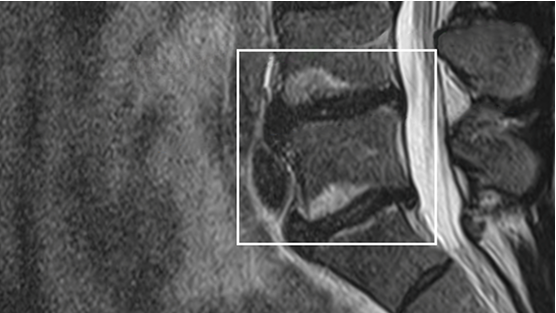

MRI scan highlighting vertebral endplates.

Photograph by Boston Scientific

The MRI is important for a diagnosis. If you have vertebrogenic pain, your MRI will likely show signs of inflammation in your endplates, called Modic changes.